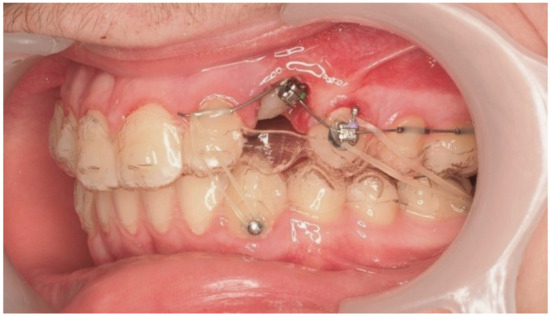

During vestibular traction, gingival removal was required. The canine presented mesial tipping and rotation. In the 14th month after the surgery, a bracket was bonded to tooth 23, following its inclination. A button was bonded on tooth 33 and connected by elastic to tooth 22 to stabilize the vertical position. Another elastic with a Class II vector was attached from the bracket on tooth 24 to a precision cut in the lower aligner (Figure 18).

Figure 18.

Vestibular traction of the canine, gingival removal, and elastic use for vertical stabilization; 14 months after the surgery.

As traction progressed, the sectional appliance was extended to tooth 21 (Figure 19). A palatal button was bonded on tooth 23 to facilitate cross elastic application for vestibular movement (Figure 20). At 20 months, the bracket on tooth 23 was progressively repositioned more cervically and mesially to aid extrusion and derotation (Figure 21). A button was bonded on tooth 22 to support a wire for additional vertical anchorage. Cross elastics were also used between the palatal side of tooth 23 and buttons on teeth 33 and 34, while another elastic connected tooth 22 to 33 (Figure 22).